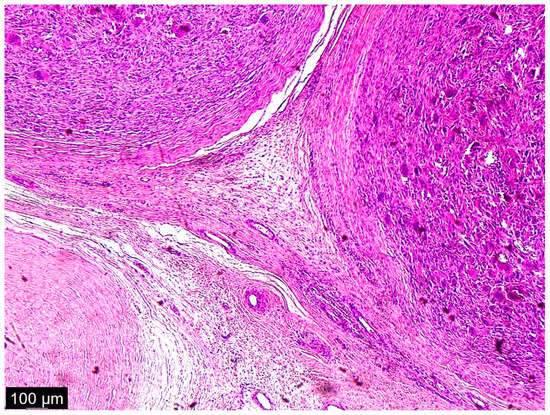

As a result of macroscopic histopathologic examination, the surgical material was described as a solid, polycyclic, cream-colored tumor, partly with a cyst. The cystic part was filled with yellow fluid. In addition, hemorrhagic changes and massive calcifications were observed within the tumor. Histopathologic examination described cytologic atypia as high grade with mitotic activity: 10/1734 mm2 and no signs of necrosis. Immunohistochemistry (IHC) results were: MDM2 (+/−) focal, CDK4 (+/−), desmin (−), myogenin (−), caldesmon (−). Numerous multinucleated giant cells with osteoclast morphology were mainly located around the hemorrhage and ossification. Amplification of the MDM2 gene was detected via fluorescence in situ hybridization (FISH). The final diagnosis was described as dedifferentiated liposarcoma FNCLCC (Fédération Nationale de Centres de Lutte Contre le Cancer), G2 (Grade 2) with osteosarcomatous differentiation, pT2 N0 (Figure 4, Figure 5 and Figure 6) [13].

Figure 5.

This picture looked like osteosarcoma, but it was not. It was a dedifferentiated liposarcoma with a heterologous component. In this case, the tumor produced osteoids with calcified trabeculae. The photo shows an osteoblastic rimming.